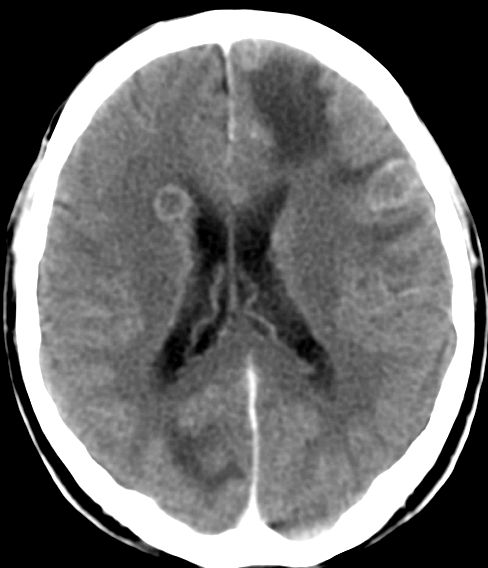

| CT: multiple Hirnmetastasen | Adenokarzinom der Lunge. CT-Untersuchung des Hirns mit Kontrastmittel. | |||

![]() |

![]() | |||